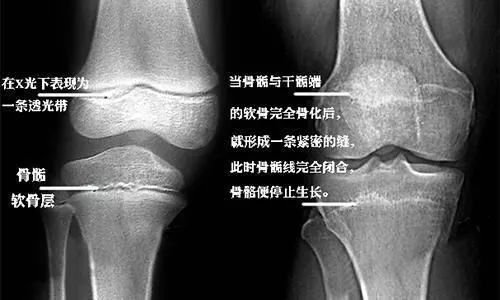

继发骨化中心又称骺部骨化中心,以长骨为例,出生时骨干大多已骨化,但骺部仍为软骨,在出生后的头几年,骺部出现骨化中心,即继发骨化中心,随年龄增长,骨化中心逐渐骨化并与骨干连接,最后只余关节软骨和骨骺板仍保持软骨的结构,以后骨骺板亦被松质骨代替,骺与干完全愈合,骨不再增长,大多数骨的干骺在25岁前完成愈合而进入成年期。